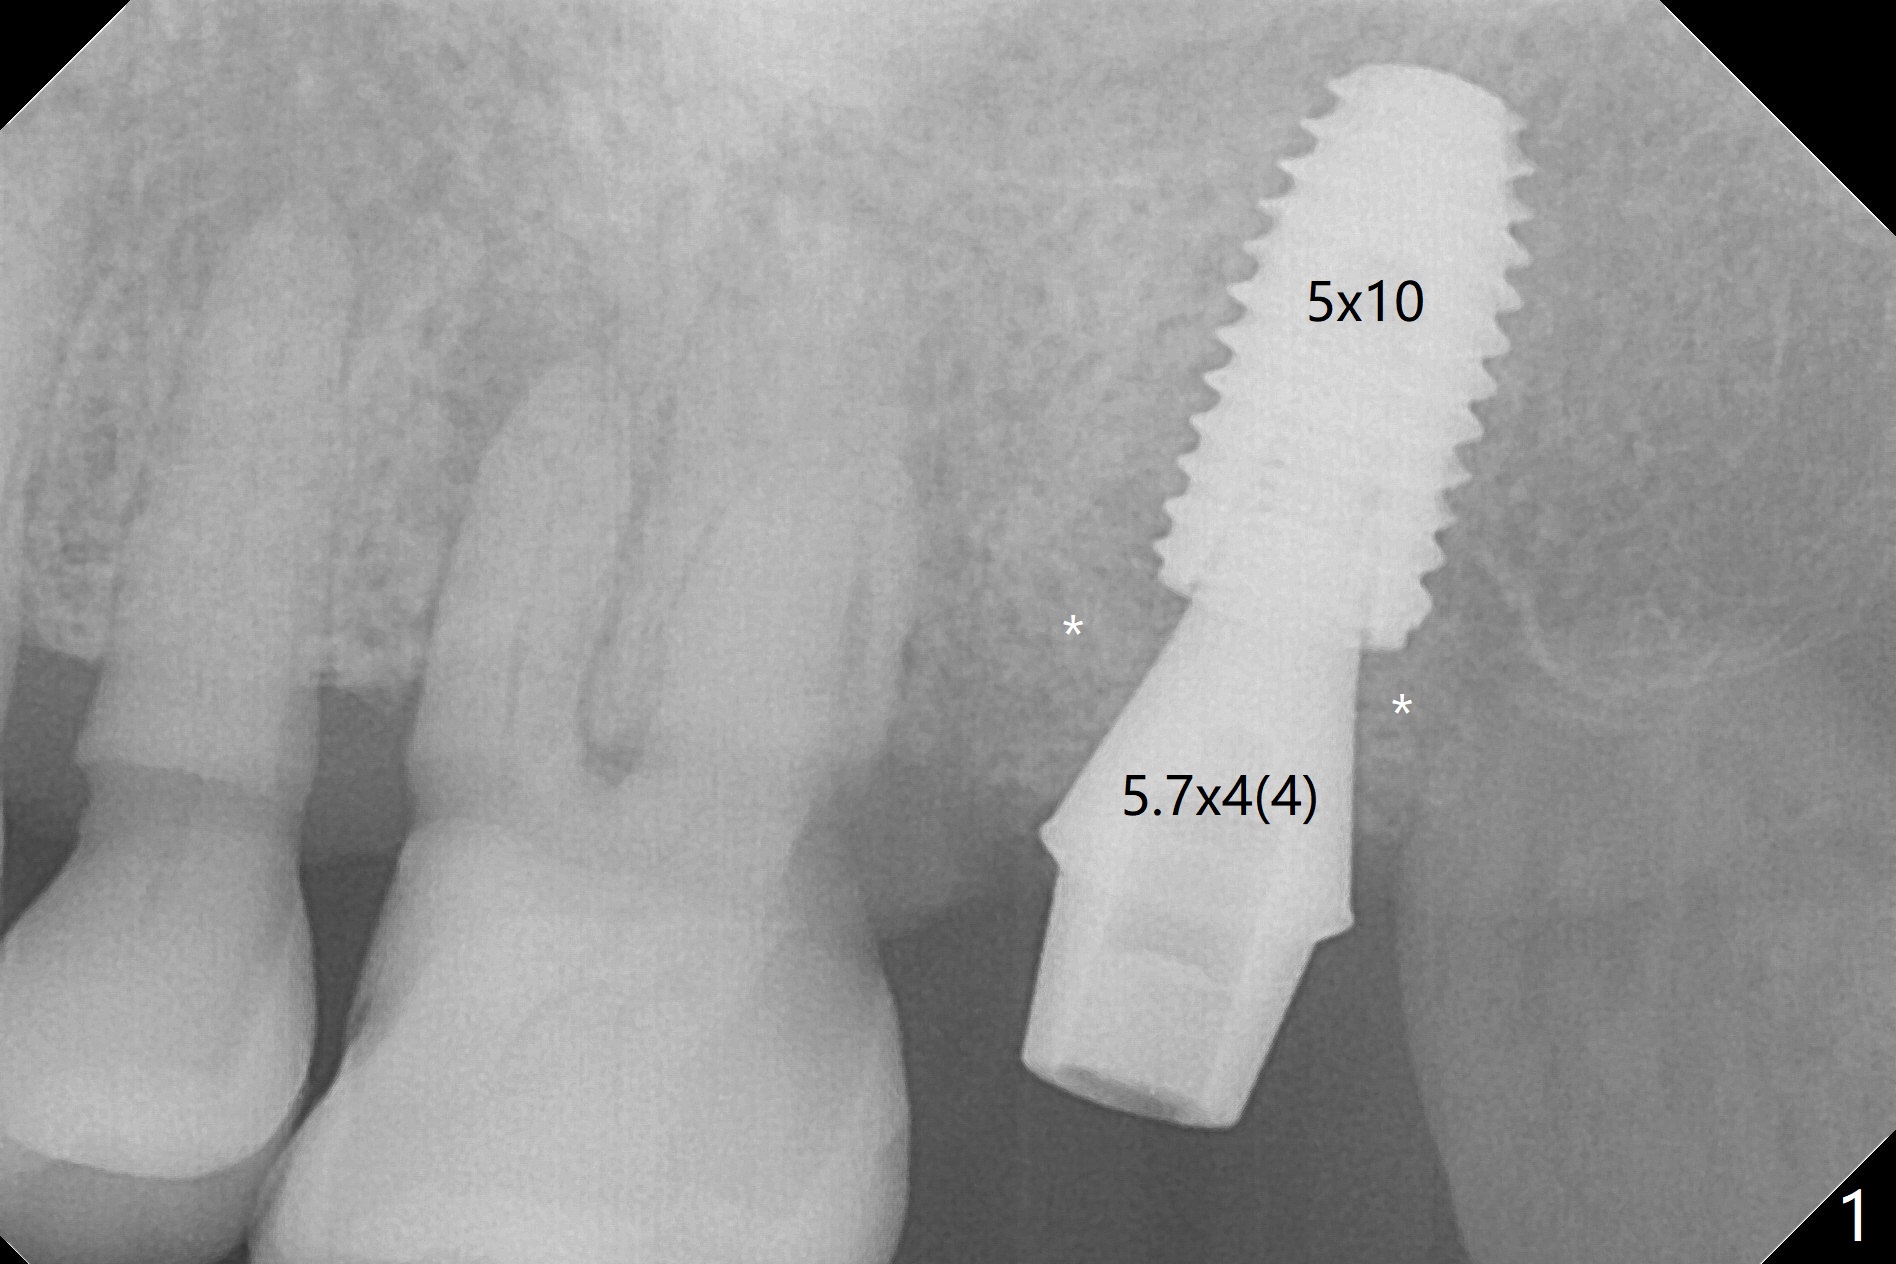

The 80-year-old woman returns for #15 extraction and immediate implant 7 months after guide fabrication. The palatal root is separated from the remaining tooth. The guide seems to be fit. The implant appears to be placed palatal with ~ 15 Ncm; a 5.7x4(4) mm abutment placed before and after bone graft (Fig.1 *). An immediate provisional is fabricated.